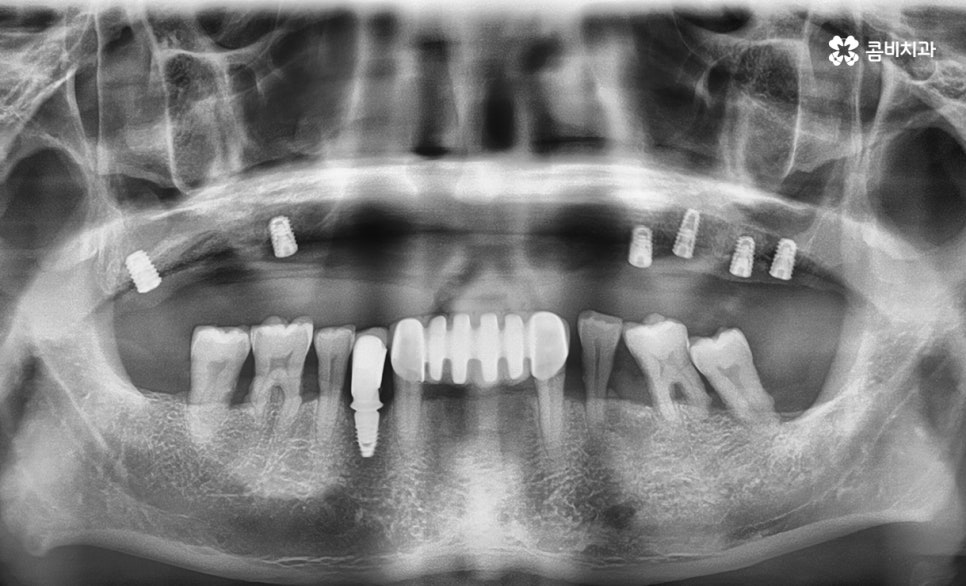

(순차적으로 임플란트 수술 진행이 되어가는 모습)

요즘은 원데이 방식으로도 많이 알려지고 있는 발치와 함께

즉시 식립을 하는 방법이 비교적 빠른 진료기간과

치주조직의 보존에 유리하다는 측면에서 선호되는 경우가 많지만

임플란트 수술 자체가 쉽지 않은 분들도 계십니다.

특히 잇몸 상태가 좋지 않은 경우에는 뼈이식을 받아야 한다거나

전악 치료의 경우 상악동 거상술과 같은 치료 과정이 필요합니다.